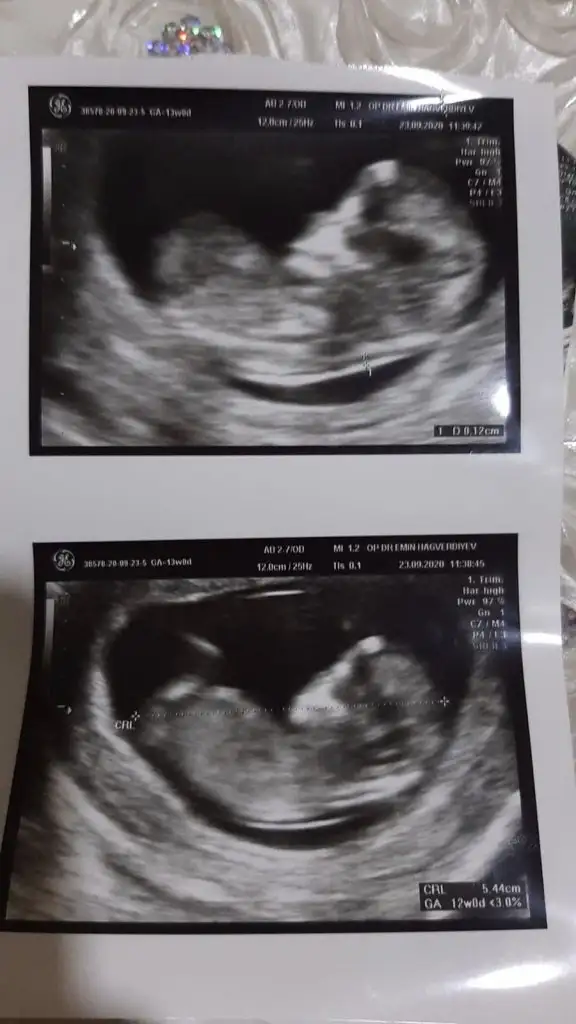

13 hafta olanı paylasin

Karından ise erkek vajinal ise kız